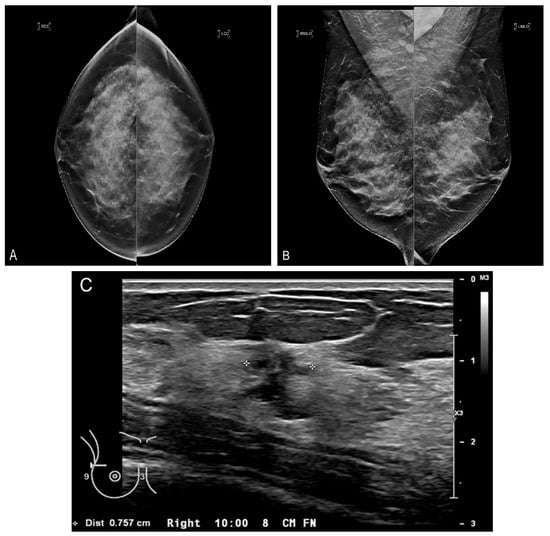

Figure 5.

Contrast-enhanced CBBCT. Left CC (A) and MLO (B) views demonstrate two masses (black and white arrows). (C) Contrast-enhanced CBBCT with gridlines marking the mass corresponding to the black arrow on mammography. (D) Contrast-enhanced CBBCT with gridlines marking the mass corresponding to the white arrow on mammography.